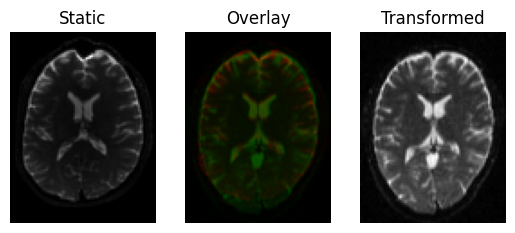

Now let’s refine with a rigid transform (this may even modify our previously found optimal translation)

This produces a slight rotation, and the images are now better aligned

transformed = rigid.transform(moving)

<Figure size 640x480 with 3 Axes>

Registration result with a rigid transform, using Mutual Information.